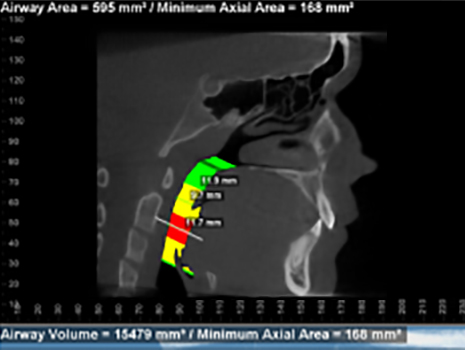

Before and after images of patient after 9 months of successful treatment: